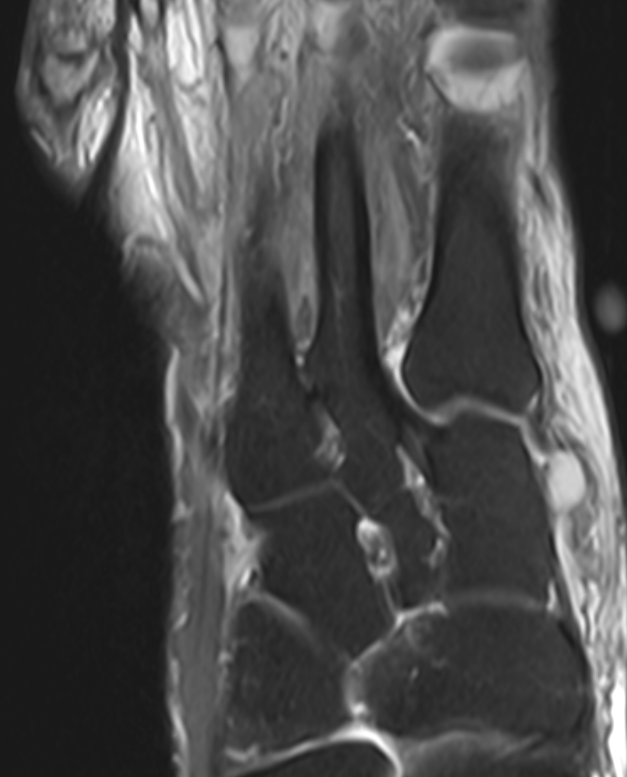

3. Lis Franc Ligament - intact